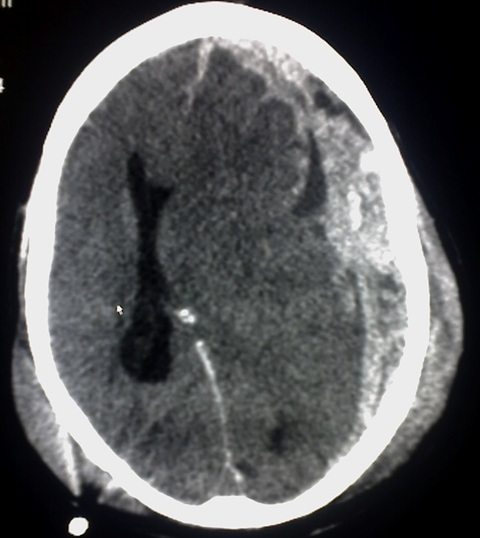

Manejo médico y/o quirúrgico de hematoma subdural, hematoma extradural, hemorragia subaracnoídea traumática, etc, así como el seguimiento posterior.